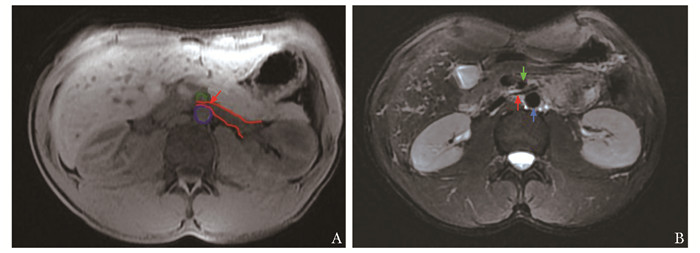

• 摘要: 胡桃夹综合征是一种罕见疾病,可导致患者出现蛋白尿、肾功能受损及生殖静脉曲张等系列症状。传统开放手术方式首选左肾静脉转位术,但手术创伤较大,术后近、远期并发症较多,影响患者生活质量。本文报道1例胡桃夹综合征合并左精索静脉曲张的男性青年患者,采用左生殖静脉-下腔静脉转流术并左精索静脉高位结扎术的手术方式,取得了良好治疗效果。该手术方式为胡桃夹综合征合并精索静脉曲张患者提供了新的治疗思路,值得临床借鉴。

Abstract: Nutcracker syndrome (NCS) is a rare disease that may cause proteinuria, renal dysfunction and varicose of genital veins. Traditional open surgery prefers left renal vein transposition, but this surgical method is more traumatic and patients often have more postoperative short-term and long-term complications affecting the quality of life. This article reports a case of a young male patient with NCS complicated with left varicocele. He was treated with left gonadal vein-inferior vena cava transposition and high ligation of spermatic vein, which achieved good results after surgery. This surgical method provides a new treatment idea for patients with NCS and varicocele, which is worthy of clinical reference.